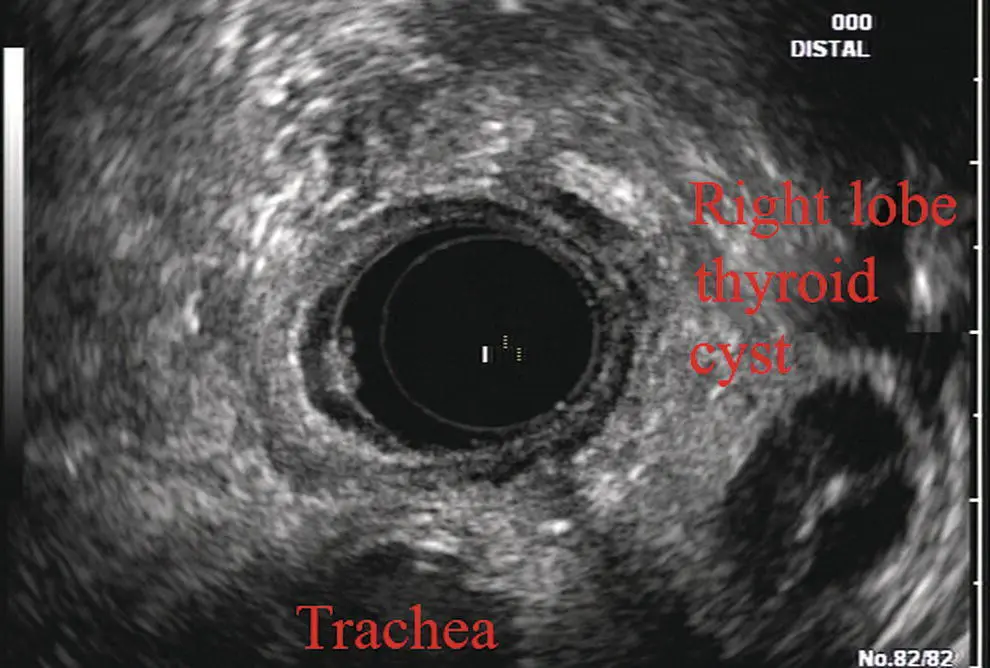

More proximally from the area at the AP window the aorta elongates and forms the aortic arch ( Figure 2.7). This usually creates a semicircle on the entire right side of the image correlating to the left‐sided arch. However, with usual orientation the aorta should not cross the midline. The left carotid and left subclavian artery can easily be seen to leave the aortic arch as small round structures on the right side of the image ( Figure 2.8). The brachiocephalic artery can sometimes be seen as well superior to the carotid on the right. As the scope is withdrawn the thyroid comes into view. For example, on the right of Figure 2.9a prominent thyroid can be seen with a cystic structure within it.

Figure 2.9 Radial array image at the level of the thyroid.